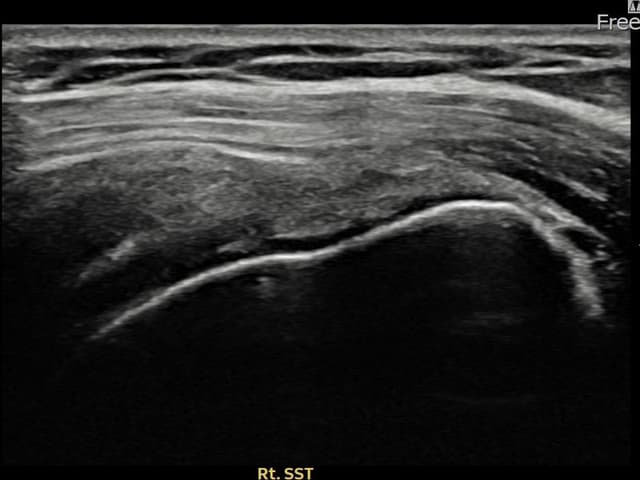

右侧 冈上肌腱 石灰化肌腱炎

13mm × 9mm